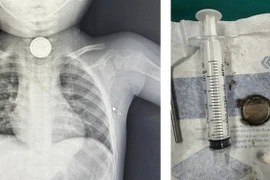

Trung tâm Y tế Nam Đàn (Nghệ An) vừa tiếp nhận và xử trí kịp thời cho một bệnh nhân 70 tuổi (trú xã Đại Huệ, Nghệ An) nuốt phải nắp chai khi uống nước.

Pin sử dụng cho các loại đồ chơi trẻ em chủ yếu là loại pin có hình dạng tròn dẹt có kích từ 10-20mm. Với kích thước như vậy trẻ khi cầm chơi viên pin cũng rất dễ dàng nuốt và viên pin có thể mắc lại tại thực quản.